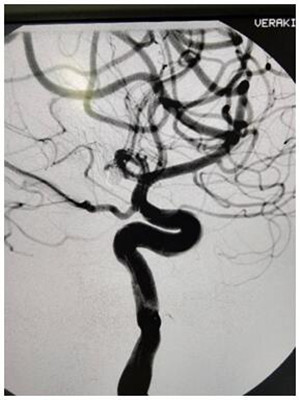

患者男性,39歲,以“頭痛2小時”急診入院,頭顱CT示:蛛網(wǎng)膜下腔出血,多考慮:動脈瘤破裂所致,需急診行腦動脈造影。護理人員在做好治療的同時,給予心里疏導,全程陪護病人,在進行3D旋轉時患者頭痛劇烈煩躁不安,造影圖像不清。為了獲取清晰的圖像準確定位,治療護士不顧輻射用自己的雙手固定住患者頭部,一旁還在患者耳邊殷殷囑咐:“這是最難受也是最重要時刻,需要配合堅持,很快就會結束!”在手術醫(yī)生嫻熟的技術下,造影順利結束。

經(jīng)過大家3個小時的努力,在姚院長準確地判斷,經(jīng)過團隊嫻熟手法和果斷地處置下,手術順利完成!麻醉復蘇后,患者清醒,頭痛緩解,無惡心,四肢肌力正常,生命體征平穩(wěn)。